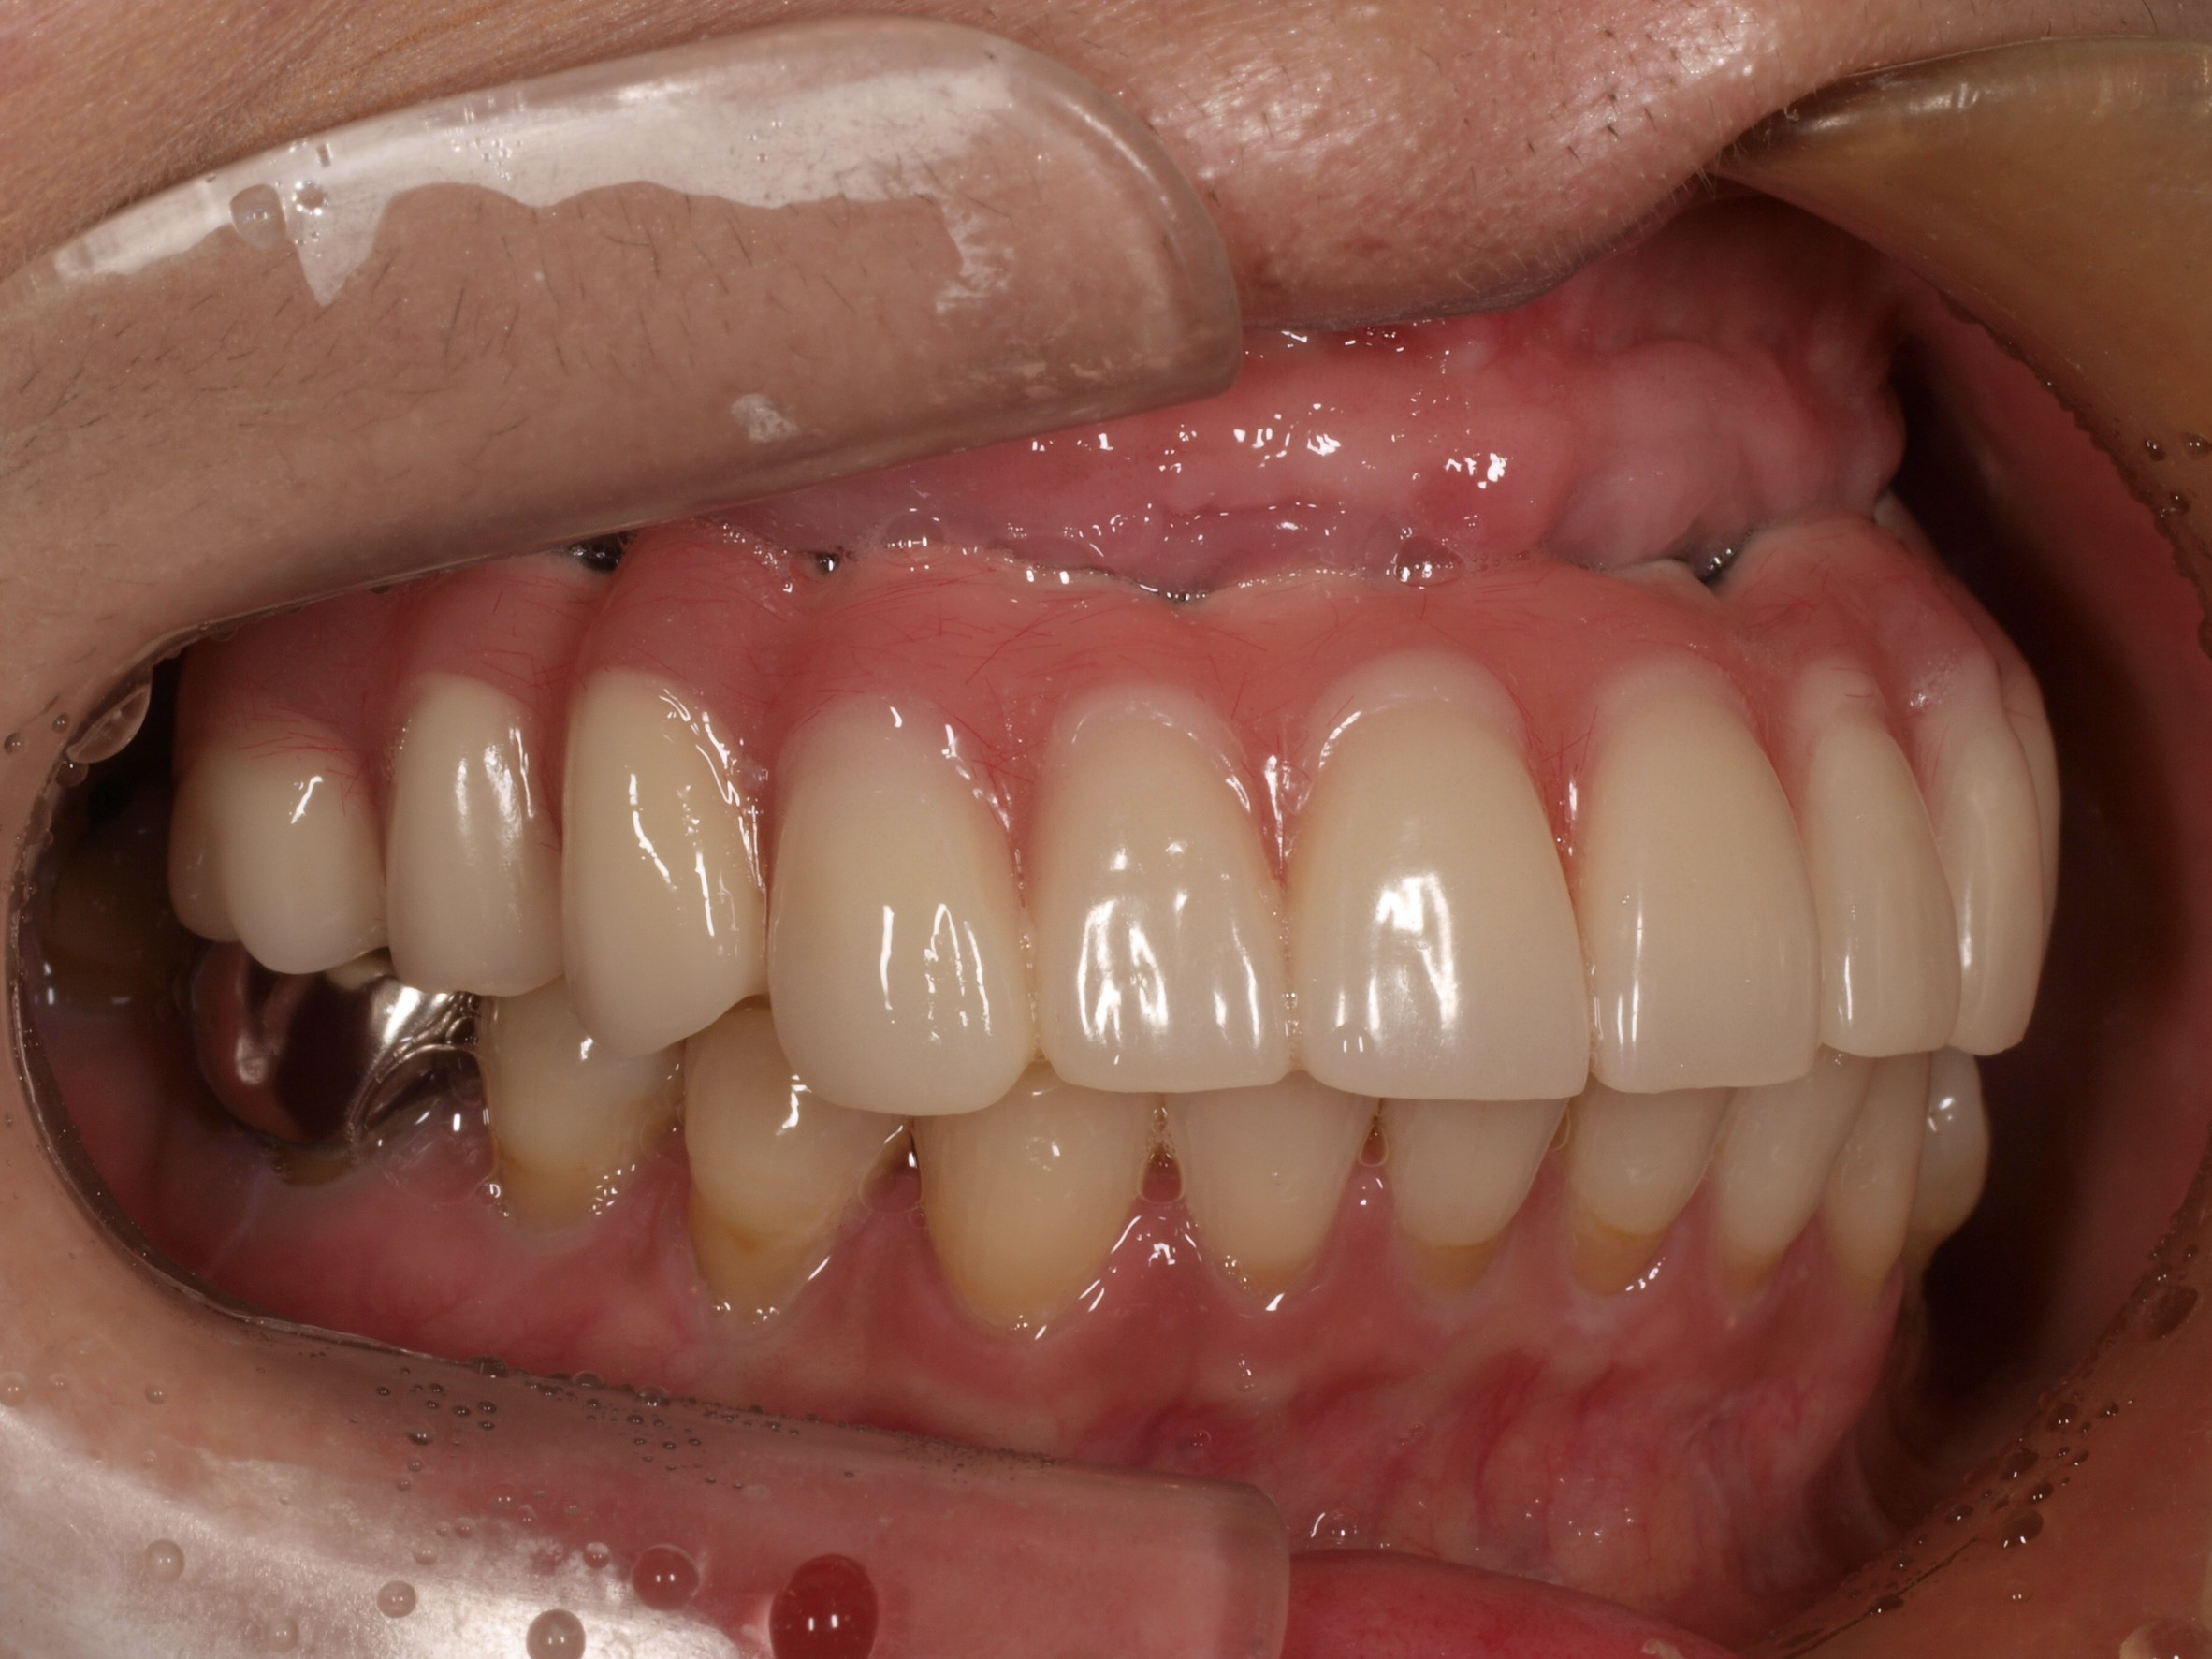

- 主訴

- 入れ歯が気持ち悪く、しっかりと食べれない。本当につらい。美味しく食べて、豊かな人生を過ごしたい。

- 処置内容

- 上顎6本(オールオン6)

- 治療費用

- 上顎350万円(税込)

- 治療期間

- 上顎1年(仮歯まで8か月)/約10回

- リスク

- 上部構造物、仮歯の破折、術後の腫れ(3日)、人工歯根脱落のリスクがあります